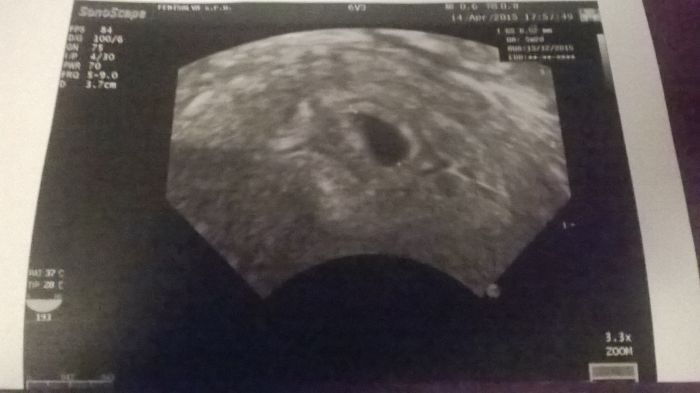

Ahoj Janičko, jsem 7+3 Určitě všechno v pořádku je, nestresuj se. Doma mám už holčičku a s ní jsem teda taky skoro žádné nevolnosti neměla ale příznaky byli a teď vůbec nic.

Ted sem 6.tyden....30dubna jdu na srdicko...tam man strach Ted celkem

Ahoj holky, špinila jsem minulý víkend a tak jsem se hned v pondělí ukázala u doktorky. Všechno bylo v pořádku a dr řekla že je to normální pokud nejde jasně červená krev. Dokonce jsem měla i bolesti jako při ms a občas se ještě objeví. Jinak je mi na zvracení, zatím všechno co sním tam zůstane, ale není mi dvakrát nejlépe. Zítra jdu na kontrolu, tak snad bude všechno v pořádku. ;-)